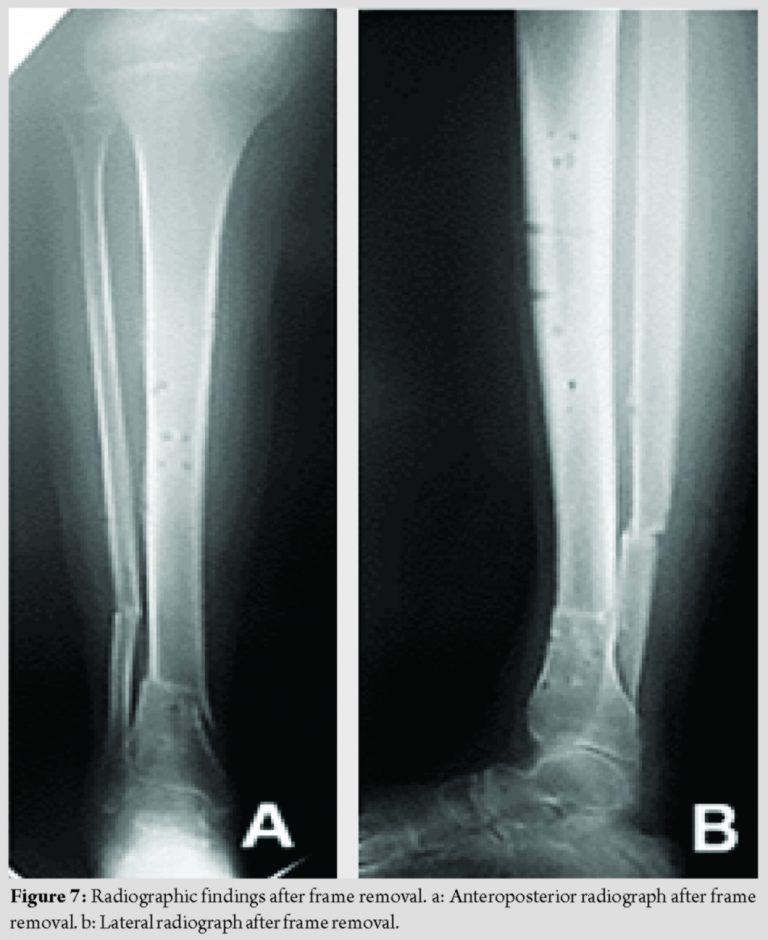

The frame was removed at 86 days postoperatively, and anatomic and functional correction was confirmed (Fig. 6). Two years postoperatively, the patient exhibited no leg length discrepancy or rotation malalignment of the lower extremities as measured both clinically and radiographically (Fig. 7).